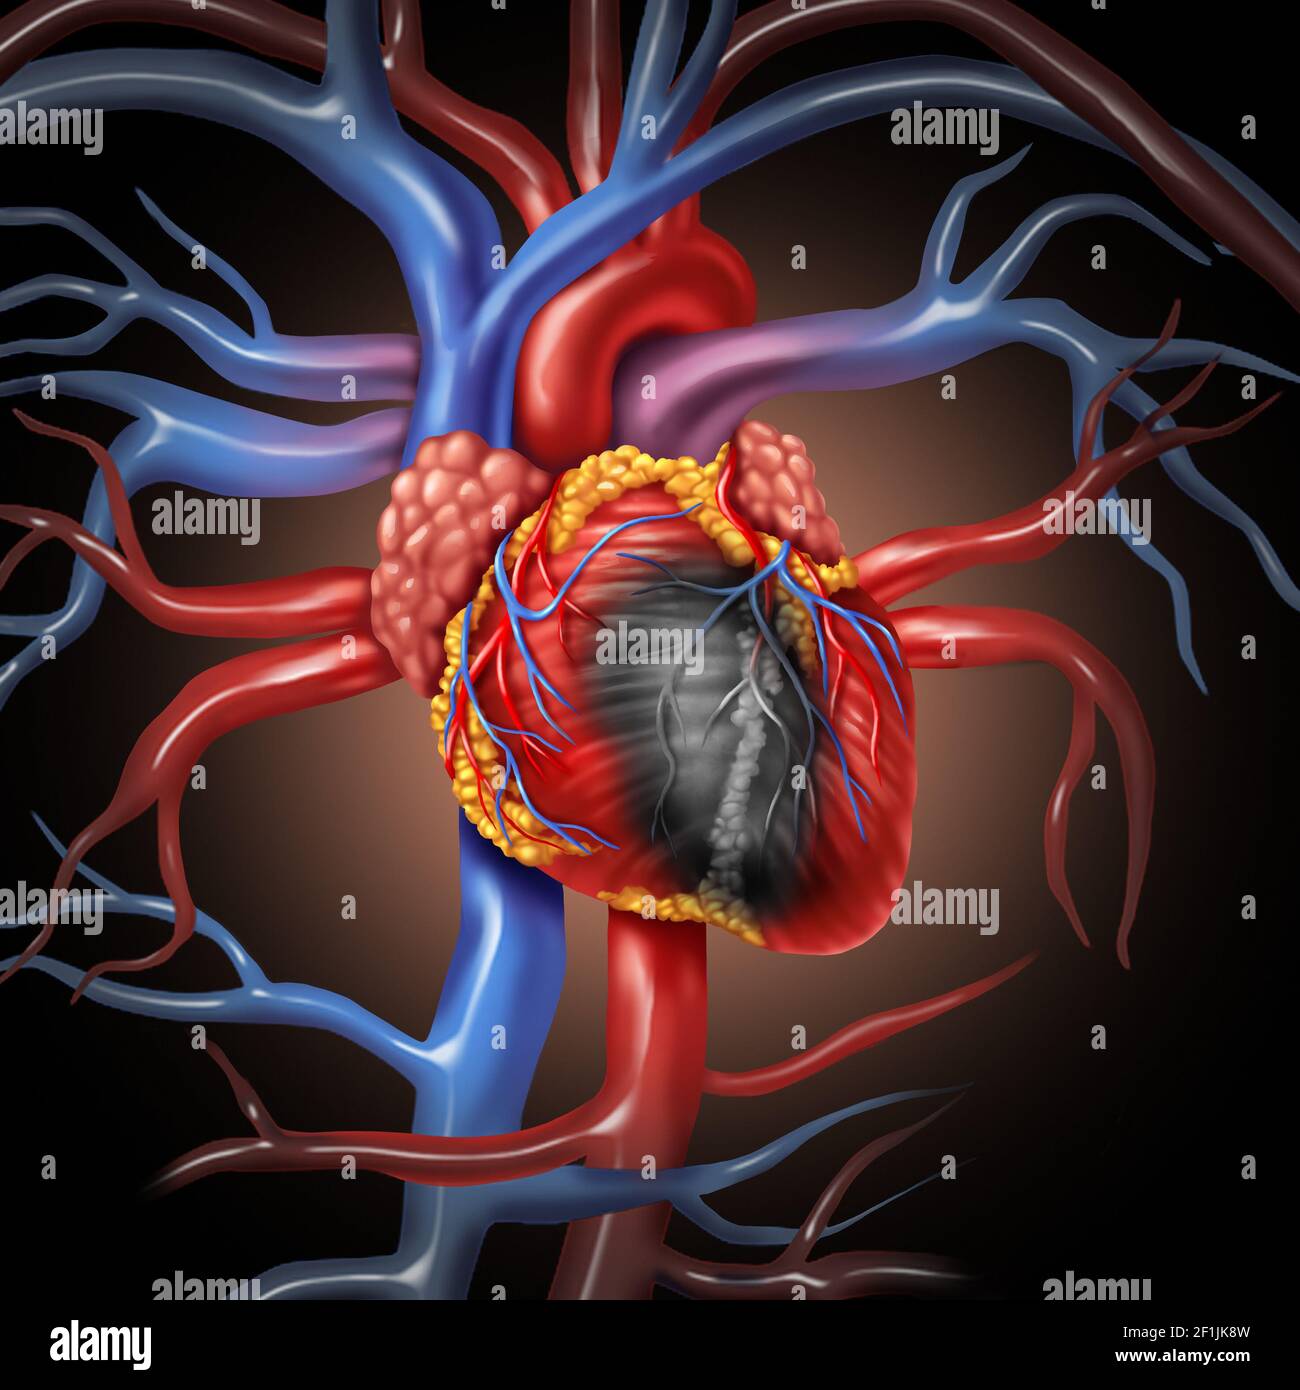

Heart disease anatomy concept and cardiovascular illness from a human organ as a medical health care symbol. Stock Photohttps://www.alamy.com/image-license-details/?v=1https://www.alamy.com/heart-disease-anatomy-concept-and-cardiovascular-illness-from-a-human-organ-as-a-medical-health-care-symbol-image414073769.html

Heart disease anatomy concept and cardiovascular illness from a human organ as a medical health care symbol. Stock Photohttps://www.alamy.com/image-license-details/?v=1https://www.alamy.com/heart-disease-anatomy-concept-and-cardiovascular-illness-from-a-human-organ-as-a-medical-health-care-symbol-image414073769.htmlRF2F1JK8W–Heart disease anatomy concept and cardiovascular illness from a human organ as a medical health care symbol.